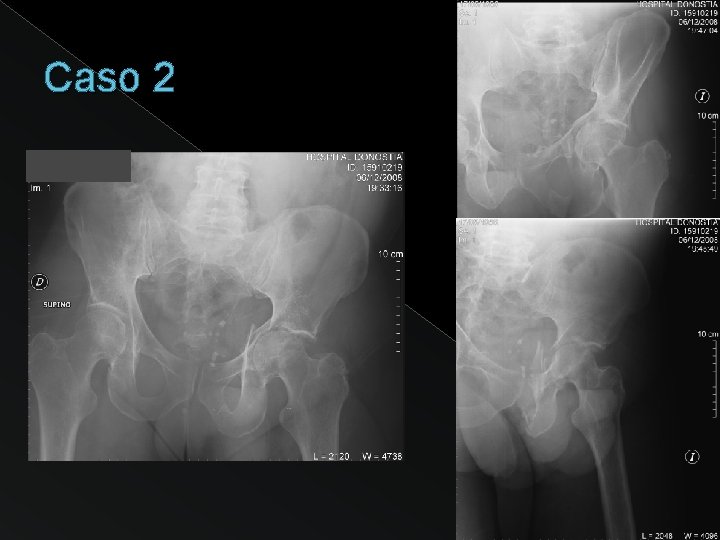

Caso 2

Disrupción del anillo obturador + SIN extensión a pala iliaca FRACTURA en “T”